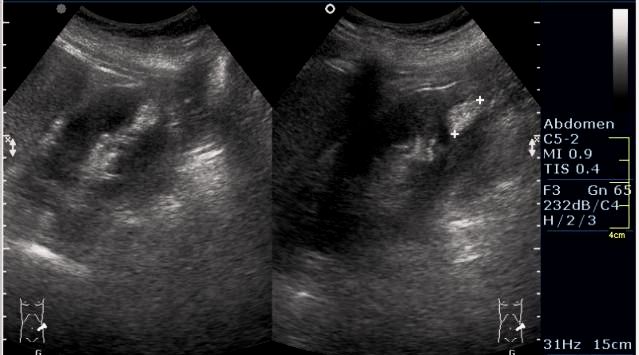

Женщина 50 лет. Жалоб нет. Обследование перед поездкой в санаторий по поводу дисфункции гепатобилиарной системы.

Случайная находка в нижней трети левой почки (не в полюсе, а по задне-медиальной поверхности).

ПО УЗ-семиотике образование соответствует ангиомиолипоме (AML). По правилам в таких случаях необходимо выполнить КТ, доказать преимущественно жировой состав опухоли, затем проводить УЗ-наблюдение.

Согласен. Именно с таким диагнозом (ангиомиолипома) отправил на КТ. Особенностью случая ИМХО является заметный "выход" образования за контур почки (на 2/3 объема).

При ультрасонографии ангиомиолипома выглядит как округлое образование без капсулы с однородной внутренней эхоструктурой и четкими контурами; эхогенность ее чаще всего равна или чуть выше эхогенности перинефральной клетчатки [7]. Значительно реже эхогенность ангиомиолипом может быть равна эхогенности почечной паренхимы; такие опухоли состоят почти полностью из гладкомышечной ткани [8]. Иногда позади ангиомиолипомы может определяться слабая акустическая тень.

Выполнена КТ. Заключение: липома.